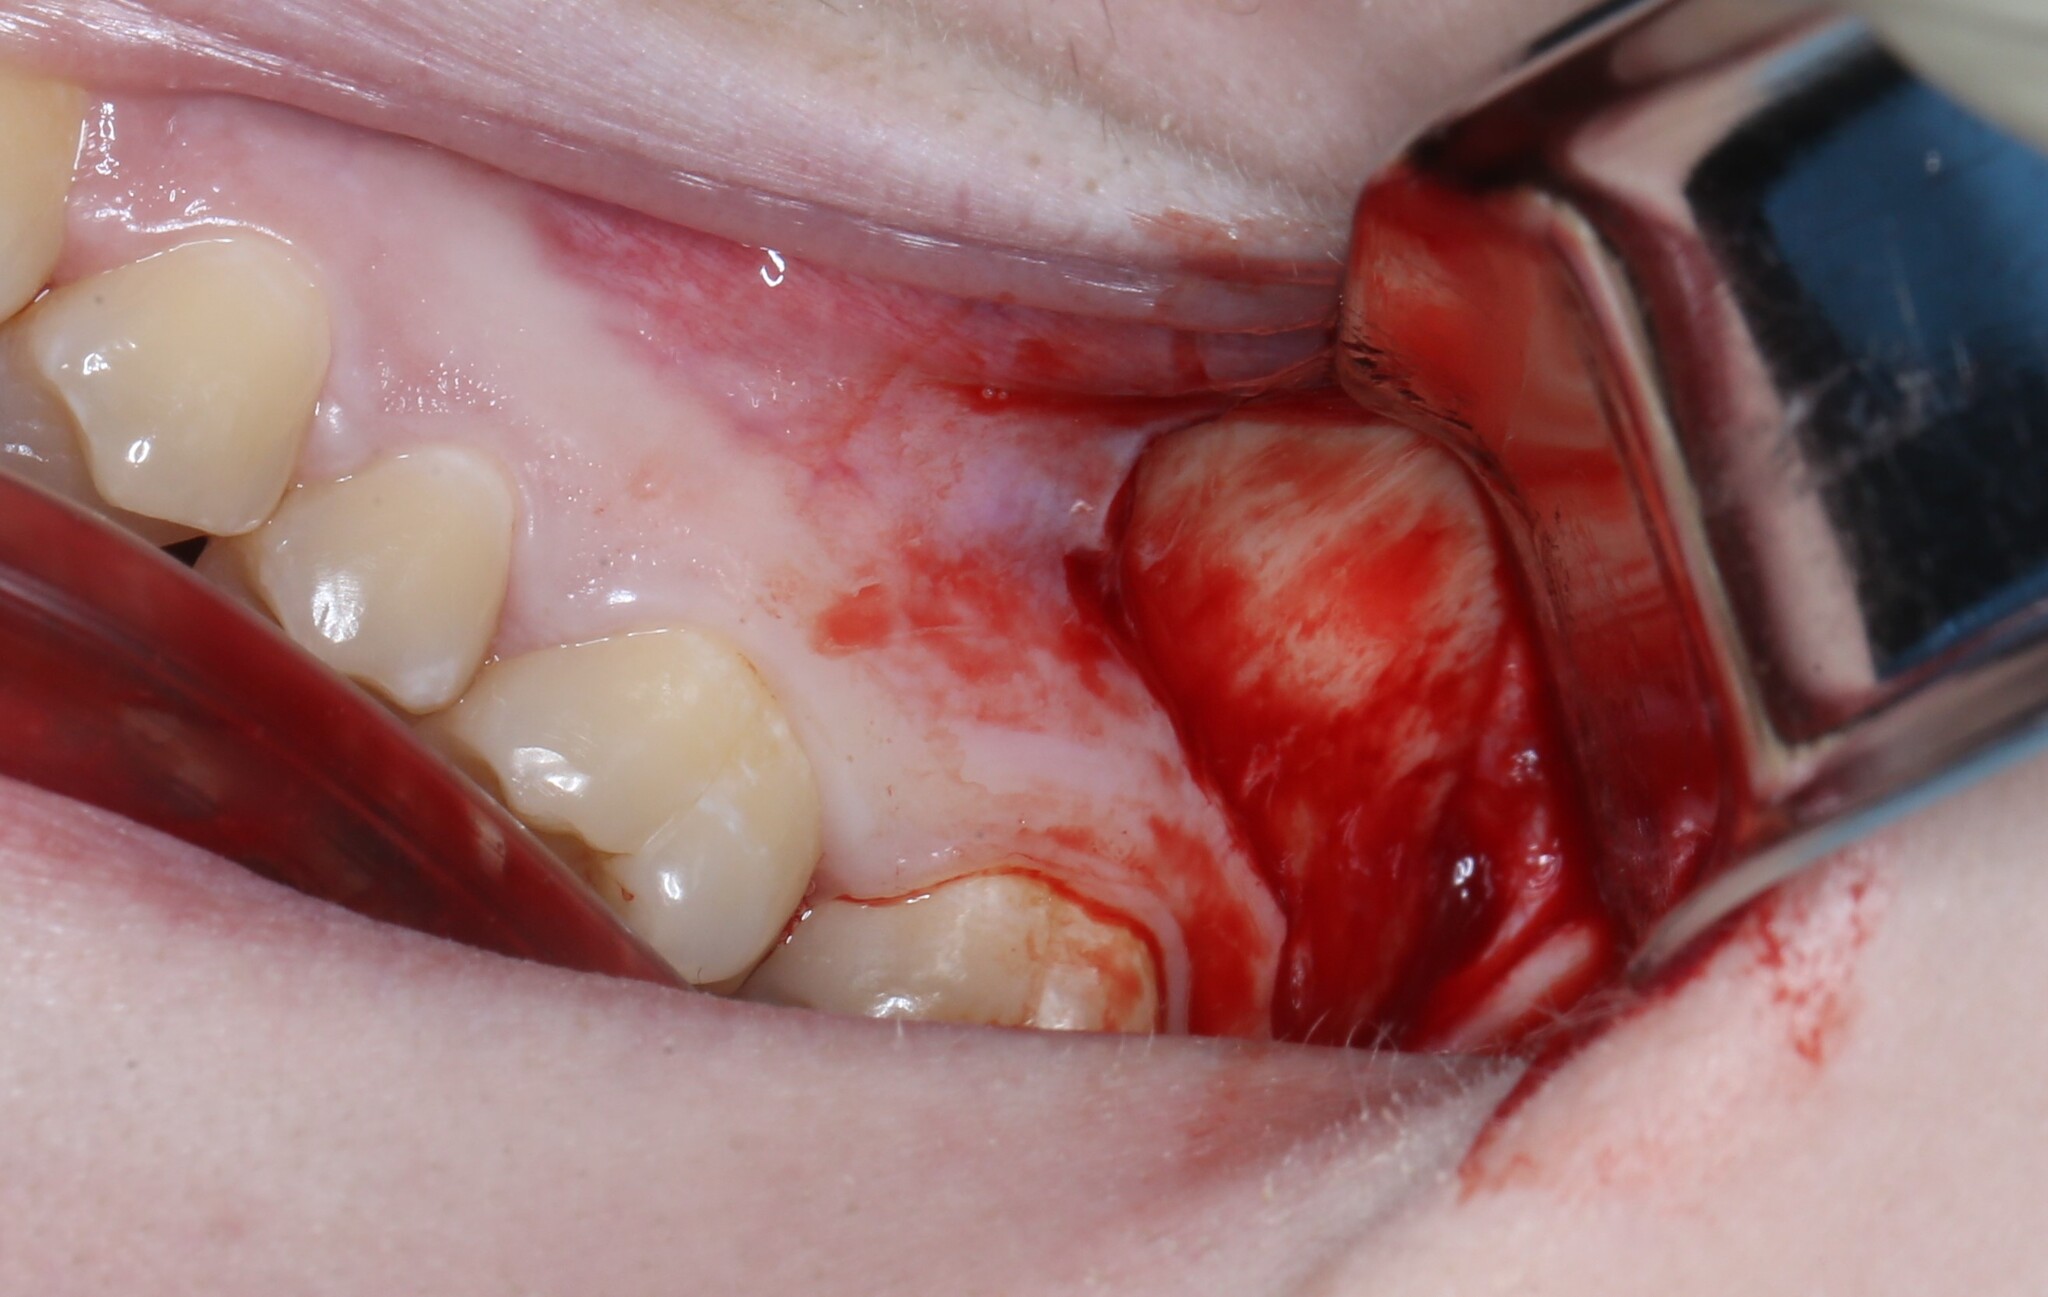

Я сделал анестезию, разрез и отслоил слизисто-надкостнечный лоскут:

Добрался до кости и при помощи специального прямого наконечника и шаровидного бора сделал окошко в проекции верхнечелюстной пазухи и удаляемого зуба мудрости:

Вооон там сверху уже можно увидеть жевательную поверхность зуба (белого цвета).

Понял, что окошко маловато. Немного «расширяемся»:

и начинаем подтягивать зуб при помощи элеватора:

Вот и он «красавчик». Берем зажим и хватаем эту мразоту за хвост, точнее за фолликул и извлекаем: